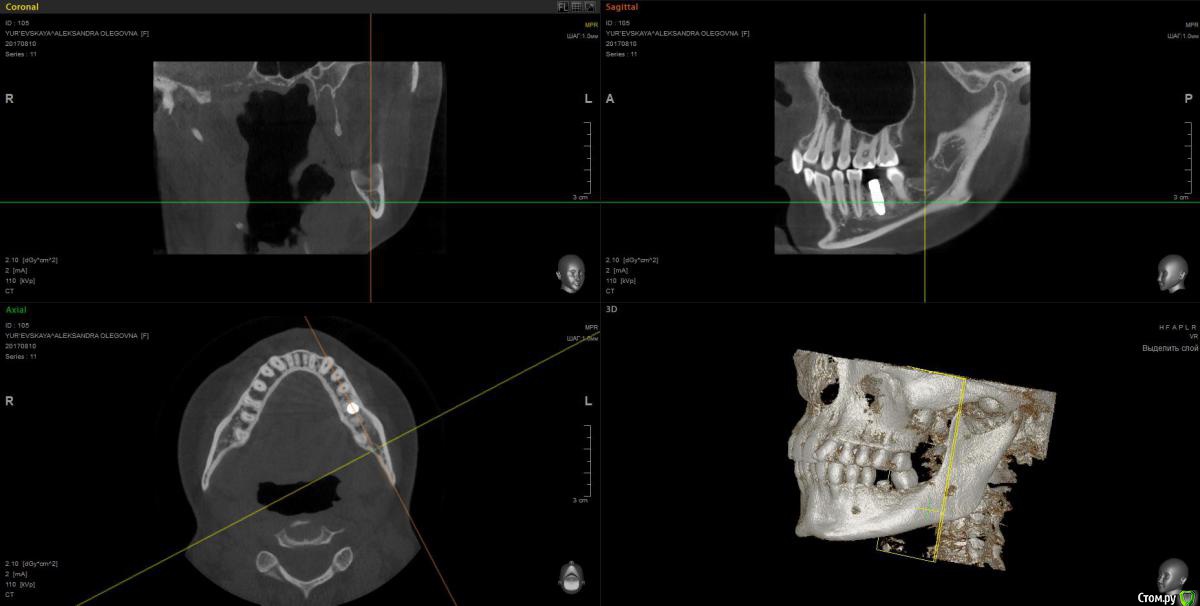

wladdX Опубликовано 28 сентября, 2017 Поделиться Опубликовано 28 сентября, 2017 Ссылка на комментарий

Павел7809 Опубликовано 28 сентября, 2017 Поделиться Опубликовано 28 сентября, 2017 (изменено) А восьмой зуб давно удаляли? Возможно это моя больная фантазия, но покрутив кт я увидел 2 канал нижнечелюстного. Посмотрел еще раз, он там точно есть Изменено 28 сентября, 2017 пользователем Павел7809 Ссылка на комментарий

Kobusha Опубликовано 28 сентября, 2017 Автор Поделиться Опубликовано 28 сентября, 2017 (изменено) А восьмой зуб давно удаляли? Возможно это моя больная фантазия, но покрутив кт я увидел 2 канал нижнечелюстного. Посмотрел еще раз, он там точно естьВосьмерку со стороны имплантата - в мае. Ретинированный зуб был. Нижнечелюстного нерва? а что это значит? =) наличие данного канала? Изменено 28 сентября, 2017 пользователем Kobusha Ссылка на комментарий

Kobusha Опубликовано 28 сентября, 2017 Автор Поделиться Опубликовано 28 сентября, 2017 (изменено) upd. по истории: сходила к имплантологу. Посмотрел кт еще раз(то, которое выше), сделал прицельный снимок. (отдавать или пересылать на почту отказались). ничего не видит. причину боли определить не может, посылает к терапевту. и хочет опять устанавливать временную коронку в ближайшее время(его рабочая версия, что в прошлый раз - коронка люфтила, давая болевой синдром). Но боль-то присутствует.Буду признательна за какие-либо альтернативные точки зрения. Изменено 28 сентября, 2017 пользователем Kobusha Ссылка на комментарий